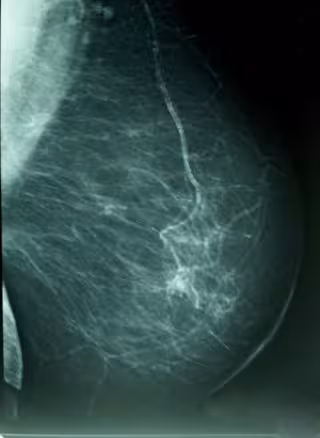

El estudio, publicado en la revista 'Breast Cancer Research and Treatment', explora la influencia de determinadas características con dicha densidad - la proporción de tejido radiológicamente blanco en la mamografía-, que es reconocido como un marcador de riesgo de cáncer de mama.

La investigación, realizada sobre una muestra 3.574 mujeres con edades comprendidas entre los 45 y los 68 años, analiza la influencia de ciertas características del nacimiento y la infancia de las mujeres con su densidad mamógrafica, un importante marcador de riesgo para cáncer de mama.

Aunque la densidad mamográfica tiene un claro componente hereditario, varía también en función de los factores de riesgo conocidos del cáncer de mama, como la edad al primer parto y el número de hijos.

Estos resultados se apoyan además en diversos estudios publicados unos años antes, en la reunión anual de 2010 de la Asociación Americana para la Investigación del Cáncer (AACR, por sus siglas en inglés) se presentaron varios estudios que mostraban cómo las mujeres con una densidad igual o mayor al 75 por ciento en una mamografía tienen de cuatro a cinco veces más riesgo de cáncer de mama que las mujeres con baja densidad.